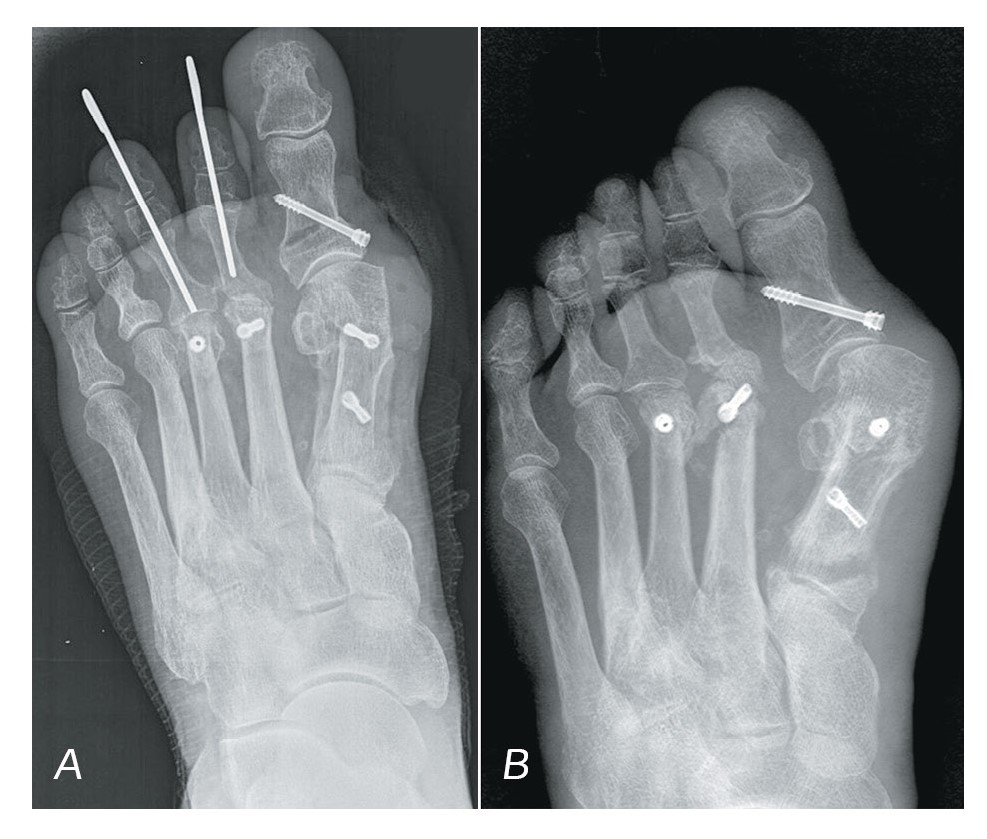

As far as isolated recurrent deformations are concerned, it is to be noted that the patients after the GRS (n=4) reported recurrent deformation of the small fingers, whereas the great toe, after the arthrodesis of the metatarsophalangeal joint and its complete consolidation, remained in the correct position. The patients who had undergone JPS, in 6 out of 8 cases reported recurrent hallux valgus (Fig. 1), the remaining two cases being characterized with deformity of small fingers. This group of patients did not report pain and complications in everyday life related to the recurrent condition.

Figure 1. X-ray image before the JPS; immediately after the deformity was eliminated; 3 months after the JPS (recurrence of the deformity); the appearance of the foot 3 months after the operation.

Рисунок 1. Рентгенограмма до проведения ССО; сразу после устраненной деформации; через 3 месяца после ССО (рецидив деформации); внешний вид стопы через 3 месяца после операции.